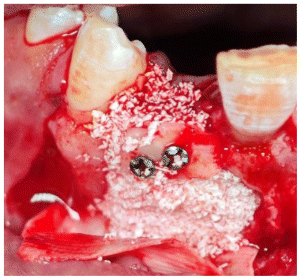

- The guide was placed and checked for correct seating. (Figure 6)

- Harvest was made with piezoelectric instruments.

- The block graft was trimmed extra orally. (Figure 7)

- The rest of the cyst defect was grafted with a mixture of auto (scraped with a bone scrapper) and xenograft (cerabone®, Botiss Biomaterials GmbH, Germany) (Figure 8)